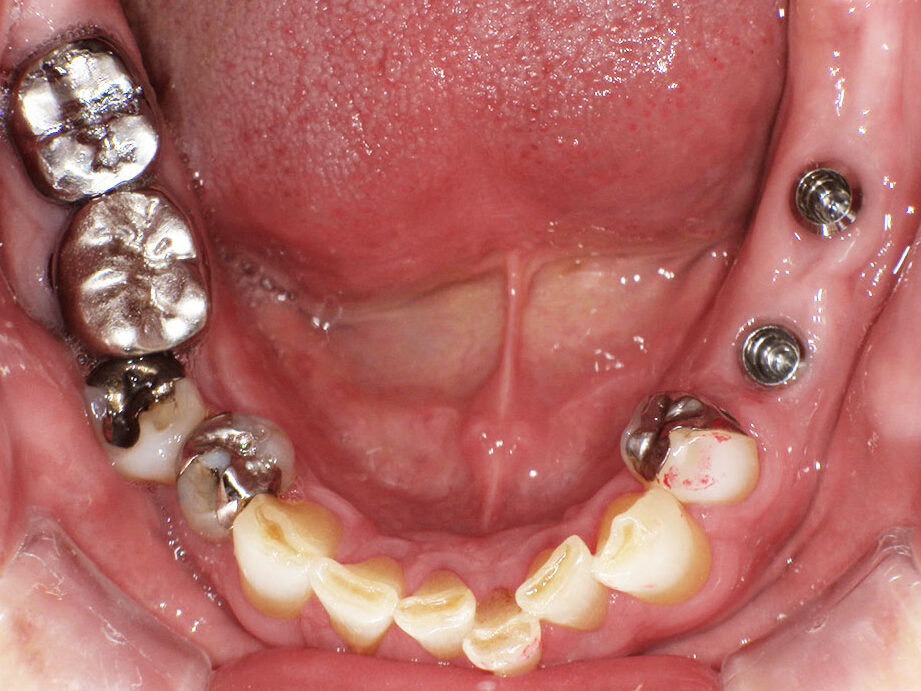

インプラントを入れた後の写真です。手術は15分程度で終わりました。術後も痛み止めを1回飲んだだけでその後は全く痛くなかったそうです。